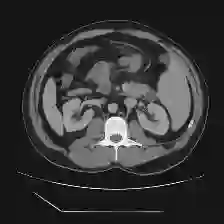

Medical image segmentation is one of the most fundamental tasks concerning medical information analysis. Various solutions have been proposed so far, including many deep learning-based techniques, such as U-Net, FC-DenseNet, etc. However, high-precision medical image segmentation remains a highly challenging task due to the existence of inherent magnification and distortion in medical images as well as the presence of lesions with similar density to normal tissues. In this paper, we propose TFCNs (Transformers for Fully Convolutional denseNets) to tackle the problem by introducing ResLinear-Transformer (RL-Transformer) and Convolutional Linear Attention Block (CLAB) to FC-DenseNet. TFCNs is not only able to utilize more latent information from the CT images for feature extraction, but also can capture and disseminate semantic features and filter non-semantic features more effectively through the CLAB module. Our experimental results show that TFCNs can achieve state-of-the-art performance with dice scores of 83.72\% on the Synapse dataset. In addition, we evaluate the robustness of TFCNs for lesion area effects on the COVID-19 public datasets. The Python code will be made publicly available on https://github.com/HUANGLIZI/TFCNs.